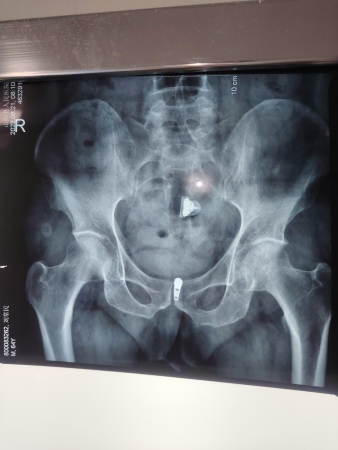

中村镇刘XX是**家属,由于积劳成疾到县级医院诊断为腰椎L4-5突出,股骨头坏死,膝关节退行性病变。经过治疗腰部没有不适,原来双侧股骨头部位疼痛不适,现在没有不适感局部也没有压痛,拍X线片显示:股骨头部略变窄毛糙;就是膝关节走路时有点不适,建议到上级医院做核磁共振检查明确诊断。